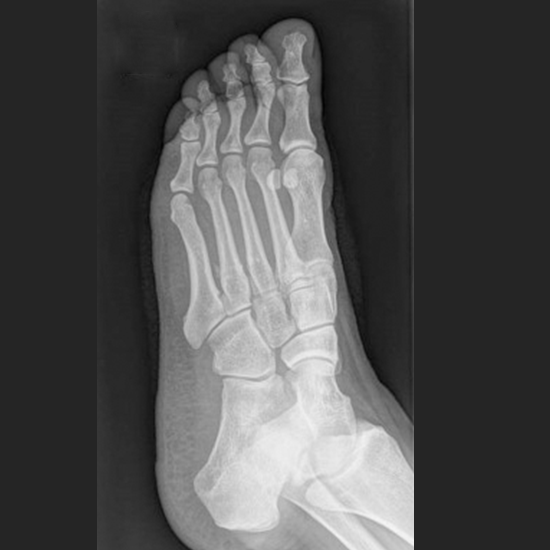

The X-ray Right Foot AP & Oblique View Test is mostly used to view the bones of your feet, including your ankle bones (tarsal bones), front end of the foot (metatarsal bones), and toes (phalanges) as well as surrounding soft tissues (skin and muscles).

To identify any broken or any fractured foot bones and also be able to track the broken bone's healing after it has been set.

To rule out any possible infection:

• Osteoporosis

• Deformities

• Irregular bone development

• Arthritis (inflammation of the joints)

• Foot Positioning: Align and then center the long axis of your foot to CR and to the long axis of portion of IR which is being exposed.

• Then rotate your foot medially to the place the plantar surface of 30 degree to 40 degree to plane of the IR. The general plane of your dorsum of the foot should be considered parallel to IR and then perpendicular to CR.

An anterior-posterior and medial oblique view would require the foot to an obliquely positioned to 30 to 40 degrees.

For Foot AP Oblique View (Medial Rotation)

A greater rotation is generally  helpful in demonstrating the joint spaces of the foot.The  Sinus tarsi will also be well demonstrated.